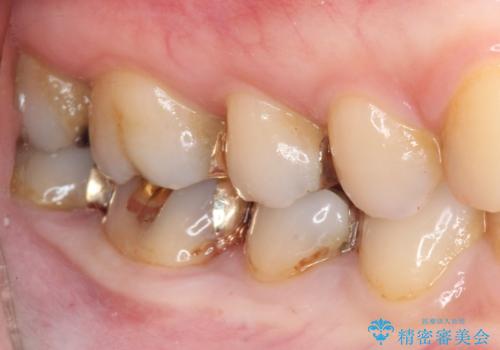

下の奥歯の虫歯をゴールドインレーで治療

- 奥歯の虫歯を心配して来院した患者様です。

レントゲン写真から、以前治療した詰め物の下に虫歯があることがわかりました。

精度が高く、虫歯の再発リスクの低いゴールドインレーで治療を行うこととしました。

ゴールドインレーは適合がよいため、虫歯の再発のリスクが少ない非常に優れた材料です。

ゴールドインレーはセラミックインレーと比べ、割れるリスクが低いため、咬合力が強い方にお勧めです。